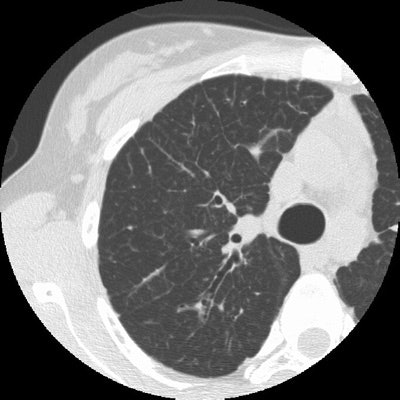

Sarcoid Stage 4:

The case below in from a patient with a history of sarcoid. The HRCT examination demonstrates interstitial lung disease with peripheral traction bronchiectasis that has been stable over the past several years. (Click image to enlarge)